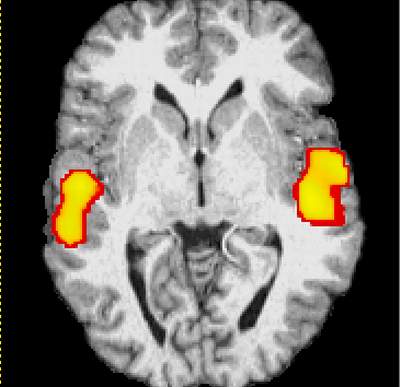

صورة للدماغ بواسطة جهاز المسح fMRI وقد تبين للعلماء أن الدماغ يبقى في حالة نشاط أثناء النوم، حيث يقوم بمعالجة المعلومات التي اختزنها طيلة النهار وترتيبها وتنسيقها في خلايا خاصة، والإشارات الصفراء على الصور هي للمناطق التي تنشط من الدماغ أثناء النوم بعد التأثير على هذا النائم بكلمات محددة. طبعاً هذه المناطق تختلف من شخص لآخر وتختلف مع نفس الشخص حسب حالته النفسية وحسب الحلم الذي يراه وهو نائم وحسب الأصوات التي يسمعها وهو نائم.